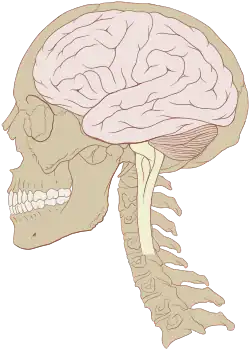

Human brain and skull | |